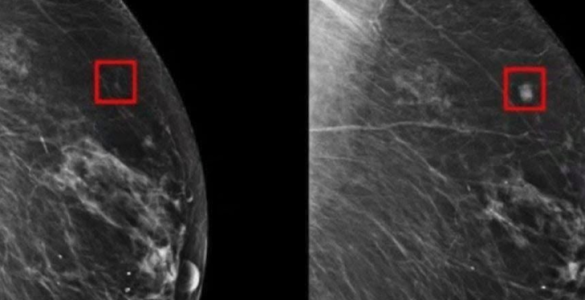

Un progresso rivoluzionario nella medicina predittiva promette diagnosi più precoci, trattamenti tempestivi e una potenziale riduzione della mortalità femminile. OSLO — Un nuovo tipo di intelligenza artificiale (IA)...